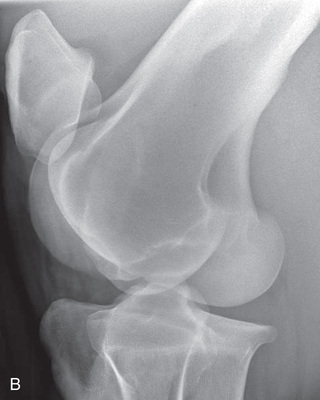

| Stifle | Lateromedial (LM) | Lateral (L) |

| Caudoproximal-craniodistal (CdPr-CrDi) | Caudocranial (CdCr) | |

| Lateral trochlear ridge and medial femoral condyle (stifle) | Caudoproximal 60-degree lateral–craniodistomedial oblique (Cd60L-CrMO) | CdLCrMO |

Radiography of the femorotibial joint (stifle) is difficult because of the thickness of the surrounding tissue and the sensitive nature of this region. Because of the depth of the muscle in the femoral region, the caudocranial projection demonstrates little above the joint space. Radiographs of this region should be attempted only if the patient is cooperative. Safety is paramount in radiography of the hind region of the horse. Sedation or a twitch may be used; general anesthesia is also to be considered.